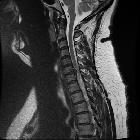

Disc protrusions are a type of disc herniation characterized by protrusion of disc content beyond the normal confines of the intervertebral disc, over a segment less than 25% of the circumference of the disc. The width of the base is wider than the largest diameter of the disc material which projects beyond the normal disc margins. The protrusion must not extend above or below the relevant vertebral endplates .

A disc protrusion is also described in terms of its axial position, into central, subarticular, foraminal, extraforaminal, or anterior locations .

Additionally, the terms contained (outer annulus fibrosus laminae are intact) and non-contained (all laminae are deficient) are also sometimes used .